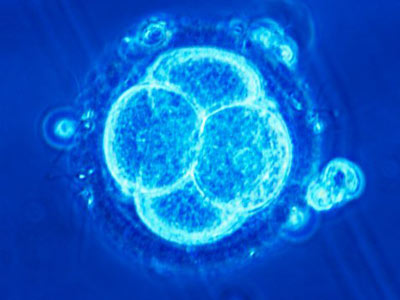

Vrhovno sodišče Združenih držav Amerike se je izreklo o izredno zanimivem vprašanju, in sicer, ali so otroci, ki so spočeti v postopku in vitro fertilizacije po tem, ko je eden od staršev preminil, upravičeni do ugodnosti preživelih, ki otrokom, ki so izgubili starša sicer pripadajo po njihovem Zakonu o socialnem zavarovanju in ugotovili, da ne avtomatično. Razsojali so na podlagi primera ženske iz New Jerseya, ki je spočela preko umetne oploditve, po tem, ko je v bitki z rakom izgubila moža, ta pa je, še za časa življenja v semenski banki zamrznil svoje seme. Vrhovno sodišče je razsodilo, da otrokom, spočetim v takih primerih ugodnosti iz socialnega zavarovanja pripadajo samo, če v določeni zvezni državi zakon določa, da otroci, spočeti po smrti starša enakovredno dedujejo njegovo premoženje, v zveznih državah pa, kjer zakona ni ali po smrti spočeti ne dedujejo avtomatično, socialno zavarovanje ti dobijo samo, če jih je pokojni imenoval v svoji oporoki.

Če vas zanima, kaj je sploh in vitro oploditev, si poglejte video.